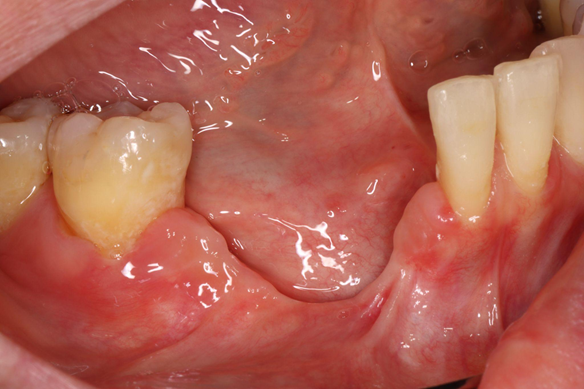

1️⃣ Pre-Op

The patient presented with missing at #43 due to implant failure and severe mobility with inflammation at #42 and #45. Teeth #42 and #45 were extracted, and after a 3-month healing period, GBR was performed to augment the ridge. However, postoperative inflammation developed, resulting in failure of graft osseointegration and necessitating an additional bone graft. At 5 months after GBR, a 6 mm short ALX implant was subsequently placed without simultaneous GBR. The implant achieved primary stability without additional grafting, impressions were taken at 4 months, and the definitive prosthesis was delivered 5 months after implant placement. At the 3-month follow-up, the restoration remained stable without complications.

At 4 months post-GBR, the grafted site showed failure with insufficient bone volume formation.

Intraoral photograph and panoramic radiograph at 4 months post-GBR.